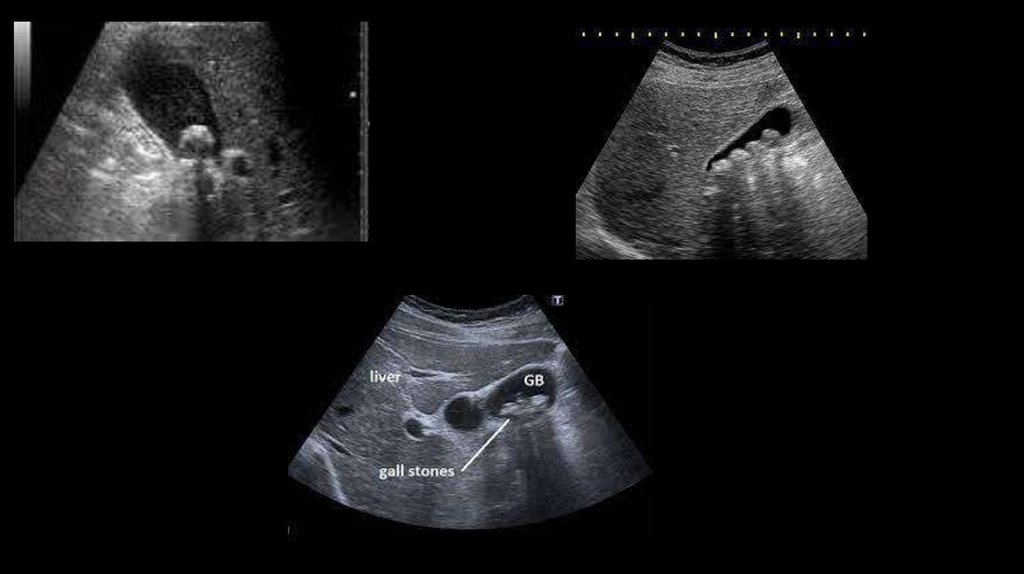

4. УЗИ органов гепатобилиарной системы

УЗИ и рентген. Рентгенологическое исследование позволяет обнаружить различные признаки морфологических или

протоков возможно радиорентгенохромодиагностическим методом. С помощью УЗИ удается установить отсутствие

конкрементов, а также дать оценку сократительной способности и состоянию стенки желчного пузыря (признаком

хронического холецистита является ее утолщение на 4 мм и более).